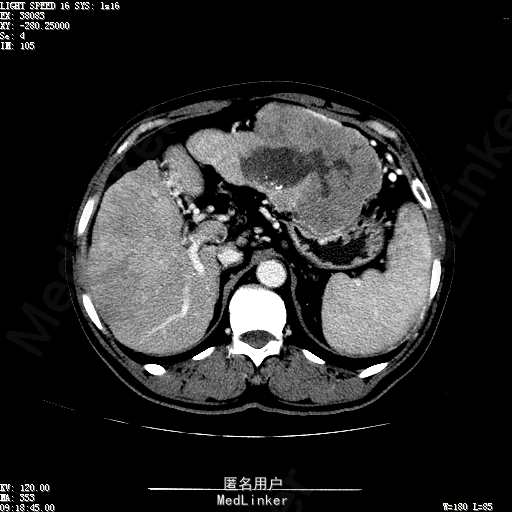

查体:生命体征平稳,神志清晰,发育正常,营养中等,体位自如,表情安静,无面容,配合检查合作。皮肤粘膜颜色正常,腹型平坦,无腹壁静脉曲张,未见胃肠型及蠕动波,无瘢痕,脐部正常。触诊:无压痛,无反跳痛,无腹肌紧张,无腹部包块。肝未触及,Murphy征阴性,脾未触及,肾未触及,无移动性浊音。 化验回报:血细胞分析(五分类):*白细胞计数 4.6 10^9/L、红细胞计数 4.27 10^12/L、血小板计数 100.0 10^9/L、血红蛋白 145 g/L、中性粒细胞百分比 68.6 %,*葡萄糖测定:葡萄糖 5.99 mmol/L,血清离子测定:*钾 4.46 mmol/L、钠 143.5 mmol/L,肾功能检测:*尿素 6.86 mmol/L、肌酐 84.2 umol/L,凝血五项:凝血酶原时间 10.7 秒、凝血酶原百分活动度 93.3 %,乙肝六项:乙型肝炎病毒表面抗原 阳性(+) 、乙型肝炎病毒e抗体 阳性(+) 、乙型肝炎病毒核心抗体 阳性(+) ,甲胎蛋白测定:甲胎蛋白 7146.00 ng/mL,ALT23U/L,AST42U/L CT检查如下图

诊断:乙肝肝硬化 静止性 代偿期 原发性肝癌 2型糖尿病 高血压病 下肢动脉闭塞征 诊断依据:1.有明确乙肝肝硬化病史 2.肝区隐痛,于外院发现肝占位,我院诊断肝癌,已行TACE治疗 3.查体:有肝掌 4.既往影像学提示肝内占位 处置:血管介入治疗:患者平卧位,以左侧肘窝为中心常规消毒、铺巾、利多卡因局麻。超声引导下,于肘横纹上方1厘米处确定皮肤穿刺点,改良Seldinger法逆行穿刺左侧肱动脉成功,置入5F血管鞘。沿导丝送入Cobra C2导管,送入降主动脉,将管头送入腹腔干,进一步送至肝固有动脉。造影见肝内广泛弥漫肿瘤染色,以右叶为主。以微导管超选肝右动脉,造影明确为肿瘤供血动脉,注入碘化油5毫升。退出微导管,经C2管注入奥沙利铂100毫克。退出C2管。拔出血管鞘,局部压迫10分钟。加压包扎。患者送返病房。